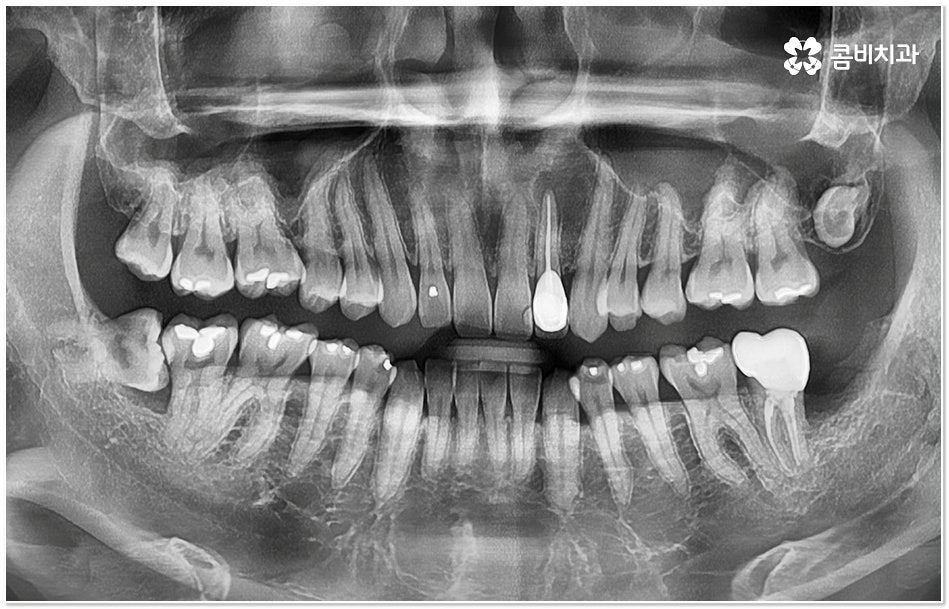

특히 그 중에서도 사랑니와 어금니 사이에 생긴 치아 사이 충치 는 구강 내 가장 안 쪽에 있기 때문에 제 때 발견하기도 어렵고 위치상 치료하기가 쉽지 않아서 병증의 진행 여부 및 상황에 따라 사랑니 뿐만 아니라 어금니까지 발치를 해야 하는 안타까운 상황에 이를 수도 있으니 그 전에 알맞은 대처를 해 주시는 것이 필요할 거예요.

충치는 입 안에 남아있는 음식물 찌꺼기 속 당분을 세균이 먹는 과정에서 배출되는 산으로 인해 치아가 부식되어 생기는 질환으로 보통 치아가 맞물리는 교합 부위인 치아의 윗면, 즉 저작면에만 충치가 생긴다고 생각하기 쉽지만 치아와 치아 사이에 생기게 되는 경우도 종종 있으며 특히 사랑니와 어금니 사이에 치아 사이 충치 가 생기면 말씀드린 것처럼 발견 및 치료가 굉장히 까다로워 질 수 있는데요.

사랑니 같은 경우는 영구치 중에서 가장 마지막에 자라기 때문에 다른 치아와 턱 뼈에 밀려 비좁은 공간에 누운 채 자리를 잡거나 부분적으로만 나오는 등 비정상적으로 맹출될 가능성이 높은 치아인데, 그렇지 않아도 위치상 관리가 잘 되지 않는 곳에서 앞 어금니와의 사이에 작은 틈새가 생기게 되면 음식물이 더욱 잘 끼고 빠지지 않으므로 치아 사이 충치 가 쉽게 발생하게 되는 거예요.

사랑니와 어금니 인접면에 치아 사이 충치 가 발생할 경우 육안으로도 보기 힘들 뿐 아니라 엑스레이를 찍었을 때에도 쉽게 발견하기 힘들 수 있기 때문에 초기에 알아차리지 못하고 치료 시기를 놓치는 경우가 종종 생기며 손상 정도가 많이 심각하거나 위치상 사랑니 발치 후에도 뿌리 끝 염증이 매우 심하거나 치아 사이 충치 로 손상이 심해 치료가 불가능한 케이스의 경우 불가피하게 어금니까지 발치를 해야 할 수 있으므로 이와 같은 상황에 이르지 않도록 평상시에 정기 검진을 꼬박꼬박 받아주는 것이 조기 대처 및 예방 등에 있어 여러 모로 유리하다고 할 수 있습니다.